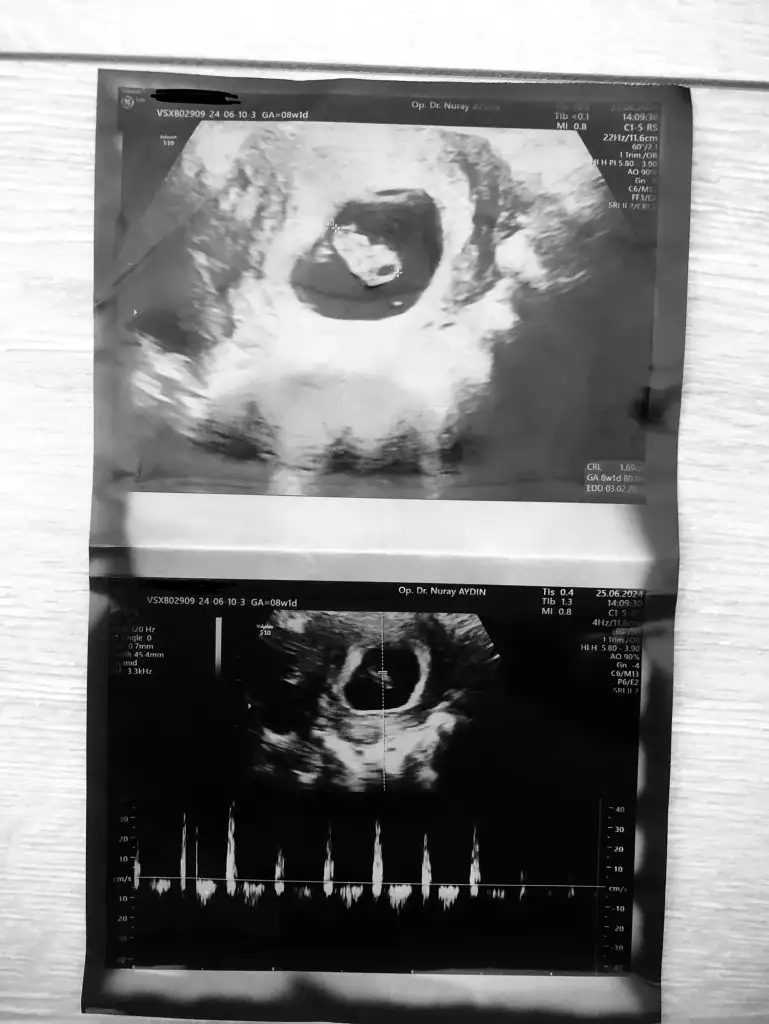

Yaklaşık 10 gündür memleketimde olduğum için buralara pek bakamadım bugün doktor kontrolüm vardı çok şükür herşey güzel, haftasını karşılıyor miniğim kalp atışımız gümbür gümbür 🥰 ilk ultrason görüntüsüyle karşılaştırınca büyüdüğünü görebiliyorum 8 haftalık olduk,herkesin hamileliği sağlıkla ilerlesin inşallah 🌸❤️

Eklentiler

• IMG_9783.webp

IMG_9783.webp

34,6 KB · Görüntüleme: 74